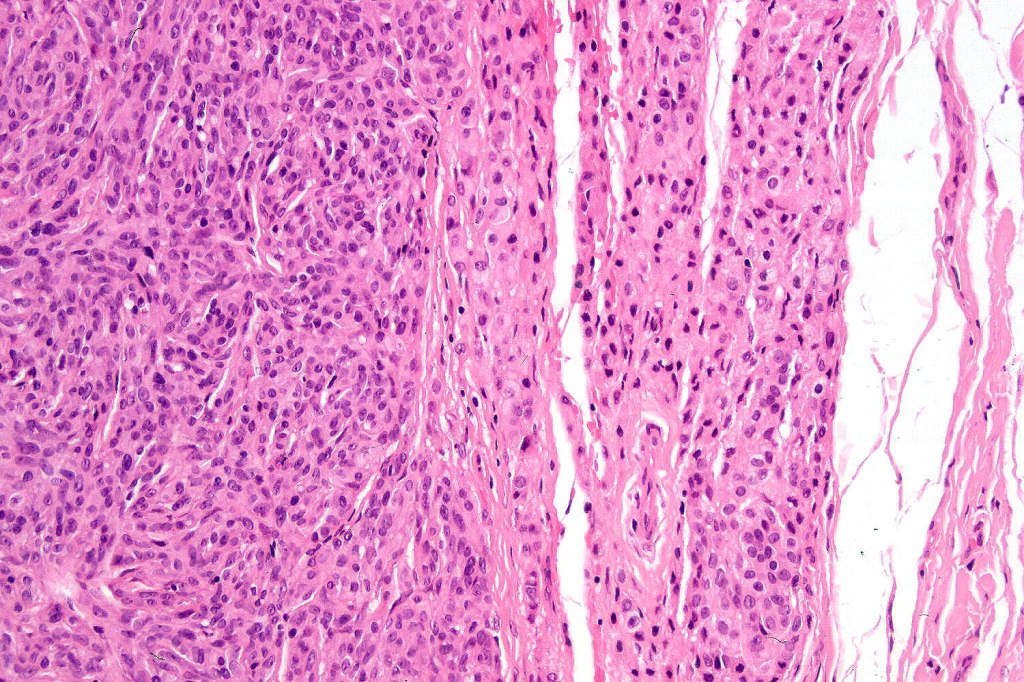

•The nodule generally merges with the adjacent nevus but sometimes it can be sharply circumscribed

•It is hypercellular and most often composed of epithelioid cells showing little pleomorphism & only occasional mitoses

•Nuleoli are small

•Intracytoplasmic pseudo-inclusions

•The constituent cells are generally larger than the adjacent nevus cells

•Some examples show more marked pleomorphism with prominent nucleoli and increased mitotic activity but abnormal mitoses are not a feature. These are not associated with any sinister biological potential

•Absence of necrosis, hemorrhage or Pagetoid spread in the overlying epidermis

•Spindle cell, small blue cell, blue nevus-like features, Spitzoid & proliferative nodules with mesenchymal differentiation (myofibroblastic, chondroid & osteoid) can be seen